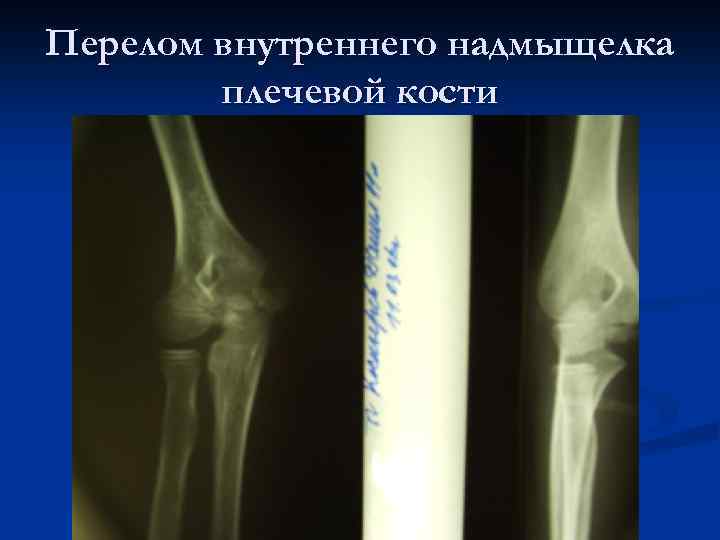

Перелом внутреннего надмыщелка плечевой кости